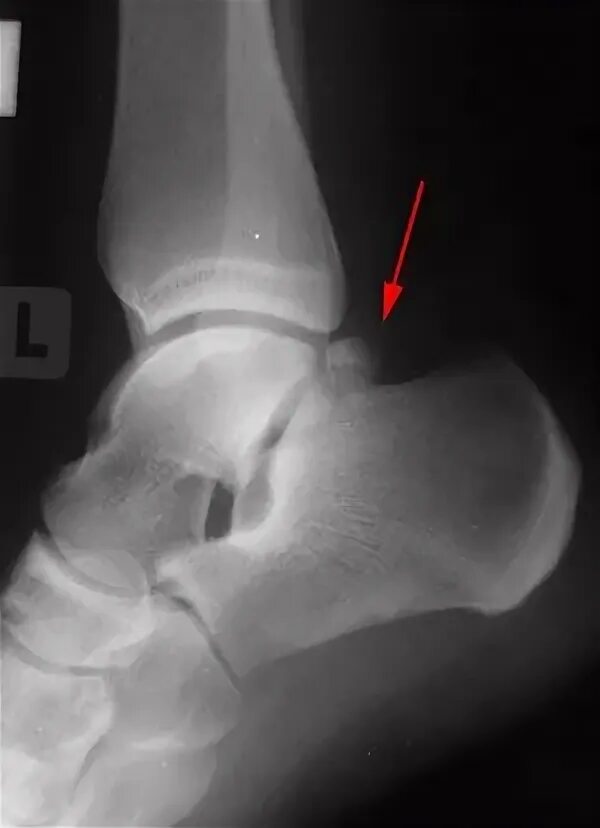

Перелом заднего